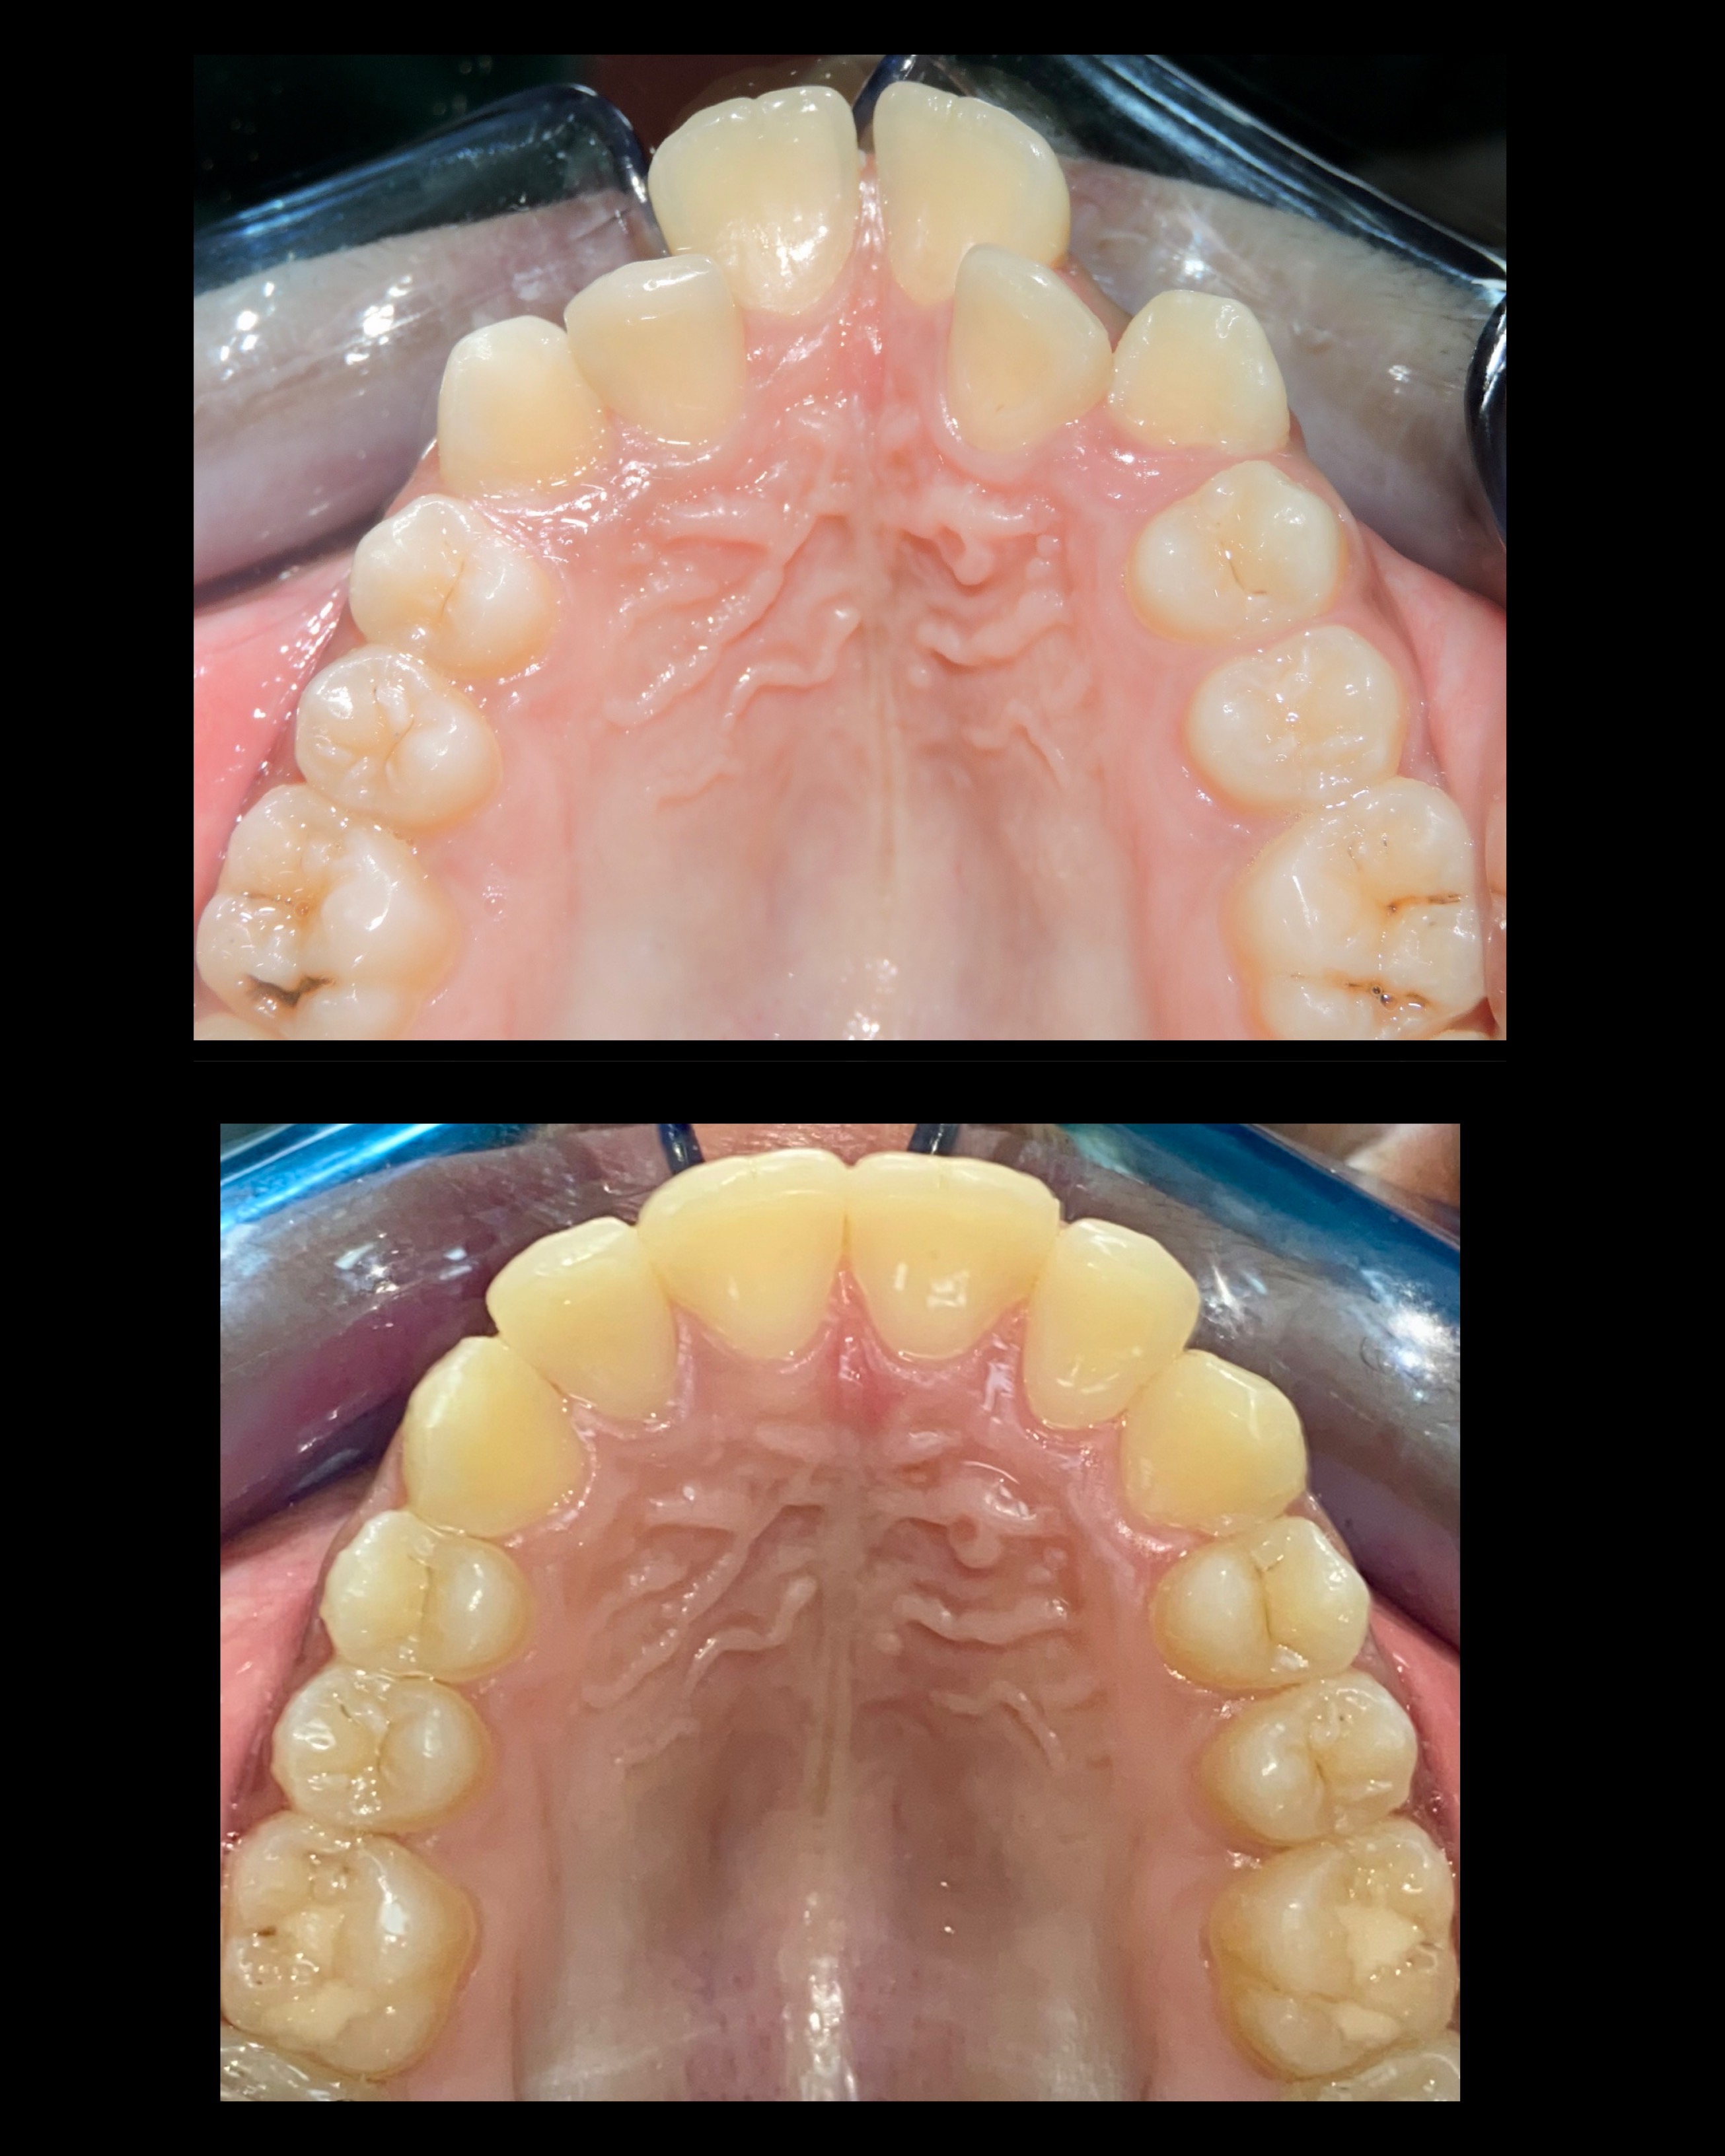

Gallery